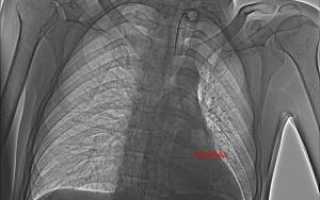

Осмотр проводит травматолог. Сначала врач выясняет обстоятельства травмы и собирает анамнез. Затем выполняет пальпацию поврежденного участка для проверки целостности костных тканей. Инструментальные исследования помогают уточнить или опровергнуть предварительный диагноз. Рентгенография позволяет оценить состояние костей грудной клетки. Магнитно-резонансная томография выявляет повреждения внутренних органов. Компьютерная томография используется для оценки состояния костных структур, если рентген не дал достаточной информации.